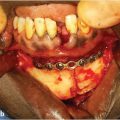

21.4 Brow Lifting

Rejuvenation of the brow is designed to address three main areas: (1) position of the eyebrow, (2) transverse wrinkles, and (3) forehead height (distance from the eyebrow to the hairline). The anatomy of the forehead muscles includes the frontalis which elevates the brow and results in the transverse rhytids. The depressor muscle includes the procerus and corrugators which cause vertical glabellar rhytids and the orbicularis oculi muscle. Various approaches to perform browlift procedures include the standard approach, the pre-hairline incision, endoscopy, direct incision, and upper blepharoplasty approach (Fig. 21‑1).

21.4.1 Open Forehead Lift

Patients with significant to severe forehead ptosis and significant asymmetry of the brows or deep forehead wrinkles may require an open or combined approach. The open approach can be very successful in re-creating lateral brow elevation. The preferred incision varies according to the sex, hair pattern, and desired elevation of the forehead. In females, an incision within the hair-bearing scalp is well tolerated and will hide the scars. It avoids shortening of the forehead, but can result in posterior displacement of the hairline. Therefore, it is best suited for patients with short forehead distances (<6 cm), and should be carefully considered in patients with high hairlines. According to Connell and Marten, every 1 mm of eyebrow elevation produces 1.5 mm of elevation of the hairline. 14 It should also be carefully considered in men at risk for male pattern baldness, as the scar will become apparent with hair loss. In bald patients, superciliary or midforehead incisions can avoid the visibility of a scalp incision and be disguised within the normal transverse forehead rhytids.

Once the incision is made, a subperiosteal dissection will provide the most reliable and lasting elevation. Gentle blunt dissection can be performed with a periosteal elevator. This allows maximum mobilization of the skin and soft tissues. Lateral dissection to release the orbital retaining ligament is helpful in obtaining lateral elevation. Several approaches have been described with particular advantages and disadvantages.

A hairline incision is preferable in patients with long foreheads (>10 cm), as it avoids lengthening the forehead. Incisions are placed perpendicular to the skin and parallel to the hair follicles, as it allows the growth of hair through the scar making it very acceptable to patients. 15 A subcutaneous approach will directly remove the skin attachments to the muscle, effectively addressing the transverse wrinkles (Fig. 21‑2).